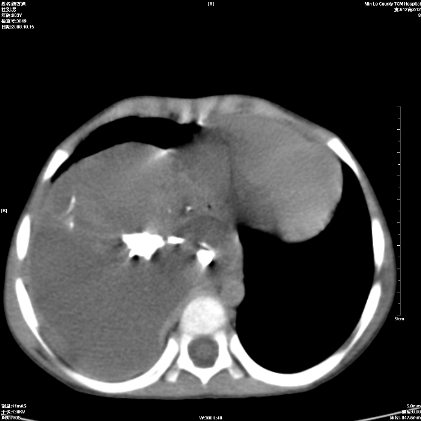

标题: PED1609:男性,3岁。彩超示肝Ca. [打印本页]

标题: PED1609:男性,3岁。彩超示肝Ca.

考虑后纵隔恶性畸胎瘤伴肝内多发转移可能性大,右侧肾上腺转移不除外.

3岁;肝低密度灶;有钙化;有转移灶;考虑肝母细胞瘤;查afp

考虑神经母细胞瘤并肝转移

考虑:1、右侧后下纵隔畸胎瘤。

2、肝脏多发血管内皮细胞瘤。

建议:增强确诊。